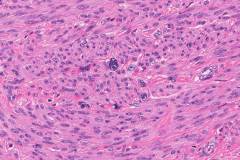

leiomyoma uterine pathology microscopic cellular dissecting leiomyomas variants mitotically bizzare nuclei epithelioid lipomatous myxoid hydropic include ilovepathology

uterus leiomyoma histology uterine uteri stepwards cat pathology cells normal figure fibroid female muscle analysis smooth resemble bmj

uterus leiomyoma atypical bizarre webpathology pathology tumor comments

leiomyoma uterus histopathology